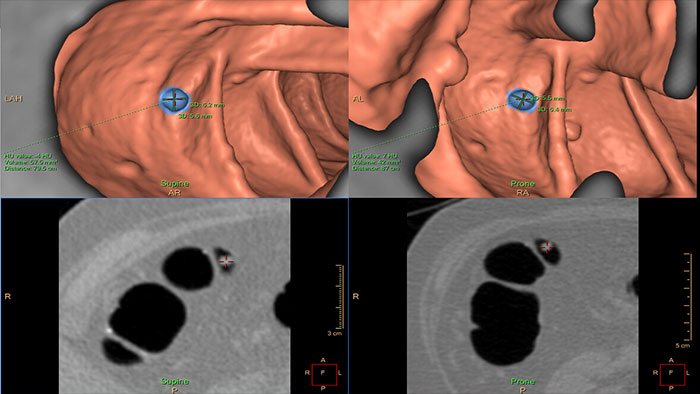

Assessing lung nodules over time

Enables review and analysis of thoracic CT images, providing segmentation, quantification and characterization of physician-indicated lung nodules. The application can be used in both diagnostic and screening evaluations, supporting Low Dose CT Lung Cancer Screening*

Reducing reading times in virtual colonoscopy

Enables 3D visualization of colon scans. The application automatically segments the air-filled colon and displays a calculated navigation path. The Perspective Filet view provides a synchronized display of the full colon surface wall with a single unidirectional view, reducing the need to review in both directions.